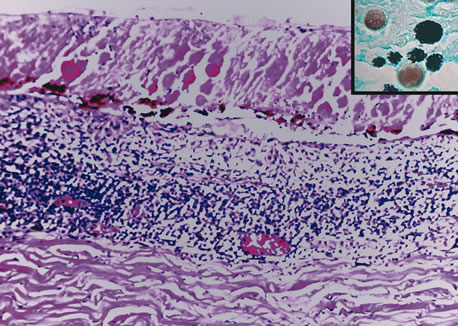

Inflammatory conditions may also lead to iris nodules. Patients suffering from fungal endophthalmitis may demonstrate an irregular yellow-white mass on the iris. Histologically, these appear as necrotizing granulomas containing mycotic agents (Fig. 2). In juvenile xanthogranuloma, a yellowish-gray iris lesion may be associated with spontaneous hyphema, and histopathologically the nodules demonstrate diffuse histiocytic infiltrate (Fig. 3). Multinucleated giant cells displaying peripheral foamy cytoplasm are also noted; these cells are known as Touton giant cells.29 The giant cells and the histiocytes contain lipid that can be demonstrated by oil red O stain.

Fig. 2. Coccidioidomycosis. Iris stroma shows necrotizing granuloma containing mycotic organisms. The organisms show features of Coccidioides immitis. (Hemotoxylin-eosin ×60.)

Fig. 3. Juvenile xanthogranuloma. The iris is infiltrated by histiocytes, which form nodular aggregates on the anterior surface of the iris. (Hemotoxylin-eosin ×25.) Inset (×200) shows oil red O-positive histiocytes.